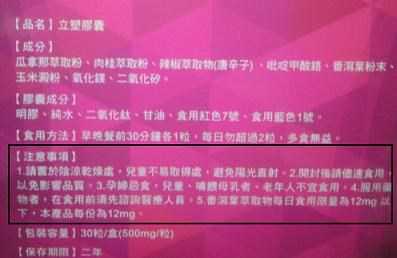

Supercut塑魔纖立塑膠囊的成分有:瓜拿那萃取粉、肉桂萃取粉、辣椒萃取物(唐辛子)、吡啶甲酸鉻、番瀉葉粉末、玉米澱粉、氧化鎂、二氧化矽。

食用方式:早晚餐前30分鐘各1粒,每日不超過2粒。(多食無益)

番瀉葉萃取物每日食用限量為12mg以下,

番瀉葉萃取物每日食用限量為12mg以下,